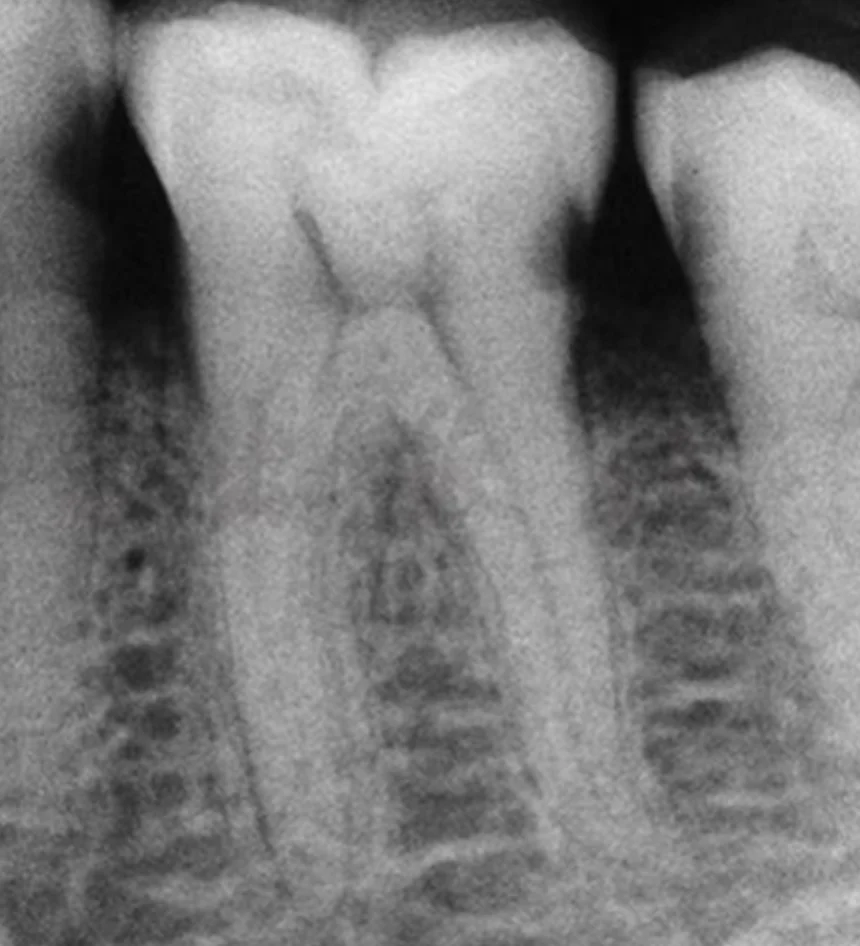

Dr.Hosam Sek

Root Canal Files

Rising

Treatment Case